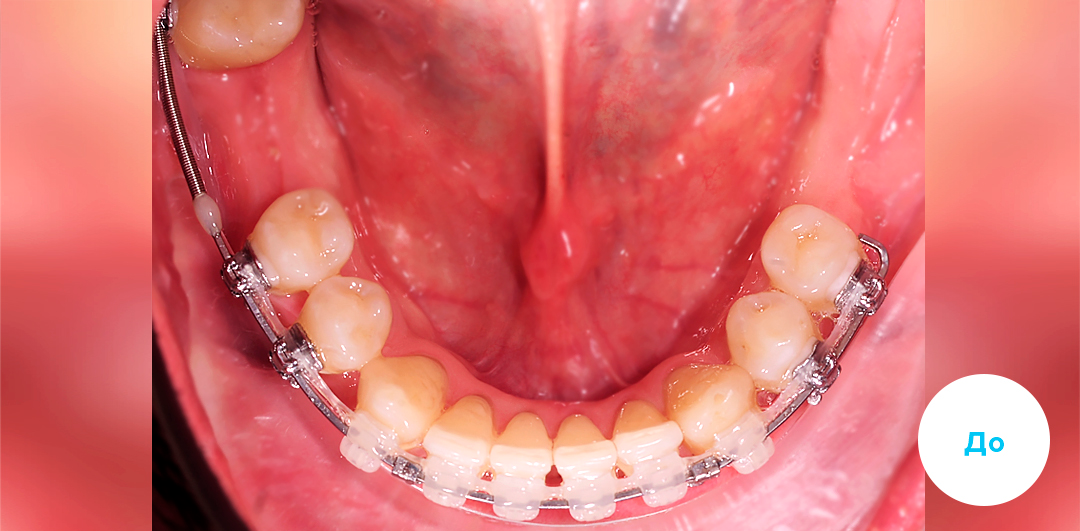

До

После

ЛЕЧЕНИЕ ДЕФИЦИТА МЕСТА НА ЧАСТИЧНОЙ БРЕКЕТ-СИСТЕМЕ У ДЕТЕЙ

Смотреть кейс